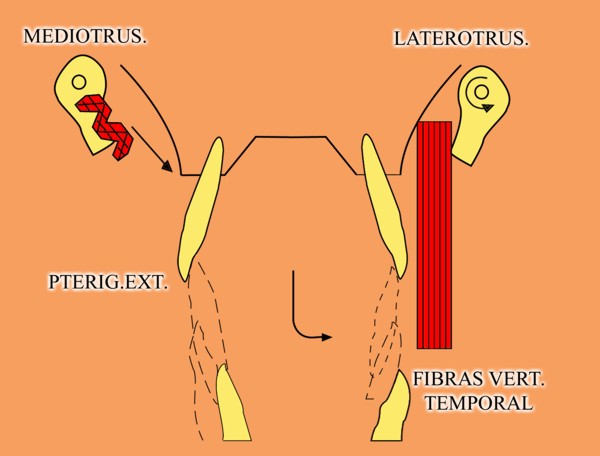

En un esquema de lateralidades a la izquierda, observamos que el Fulcrum de la misma lo encontramos en el cóndilo izquierdo, Cóndilo de Trabajo, la Potencia se encuentra en la fuerza generada por el Pterigoidéo Ext. del lado derecho, Cóndilo de No Trabajo, y la resistencia se dispone, en el caso de una FUNCIÓN DE GRUPO, en las Crestas Triangulares Internas de la tabla premolar-molar superior, que rozan contra las Crestas Centrales antagonistas ,correspondientes al inferior.

Por lo tanto, el Brazo de Potencia se establece entre el CnT(POTENCIA),y el CT(Fulcrum), mientras que los Brazos de Resistencia de las distintas piezas que intervienen en la Función de Grupo, se encuentran entre estas piezas y el CT(Fulcrum).

Como podemos ver en el esquema, estos son menores que el Brazo de Potencia y por lo tanto la fuerza generada por el mismo, producirá mayor deterioro , pues la palanca no está equilibrada:

EL BRAZO DE POTENCIA ES MAYOR QUE EL DE RESISTENCIA (Fig.6)